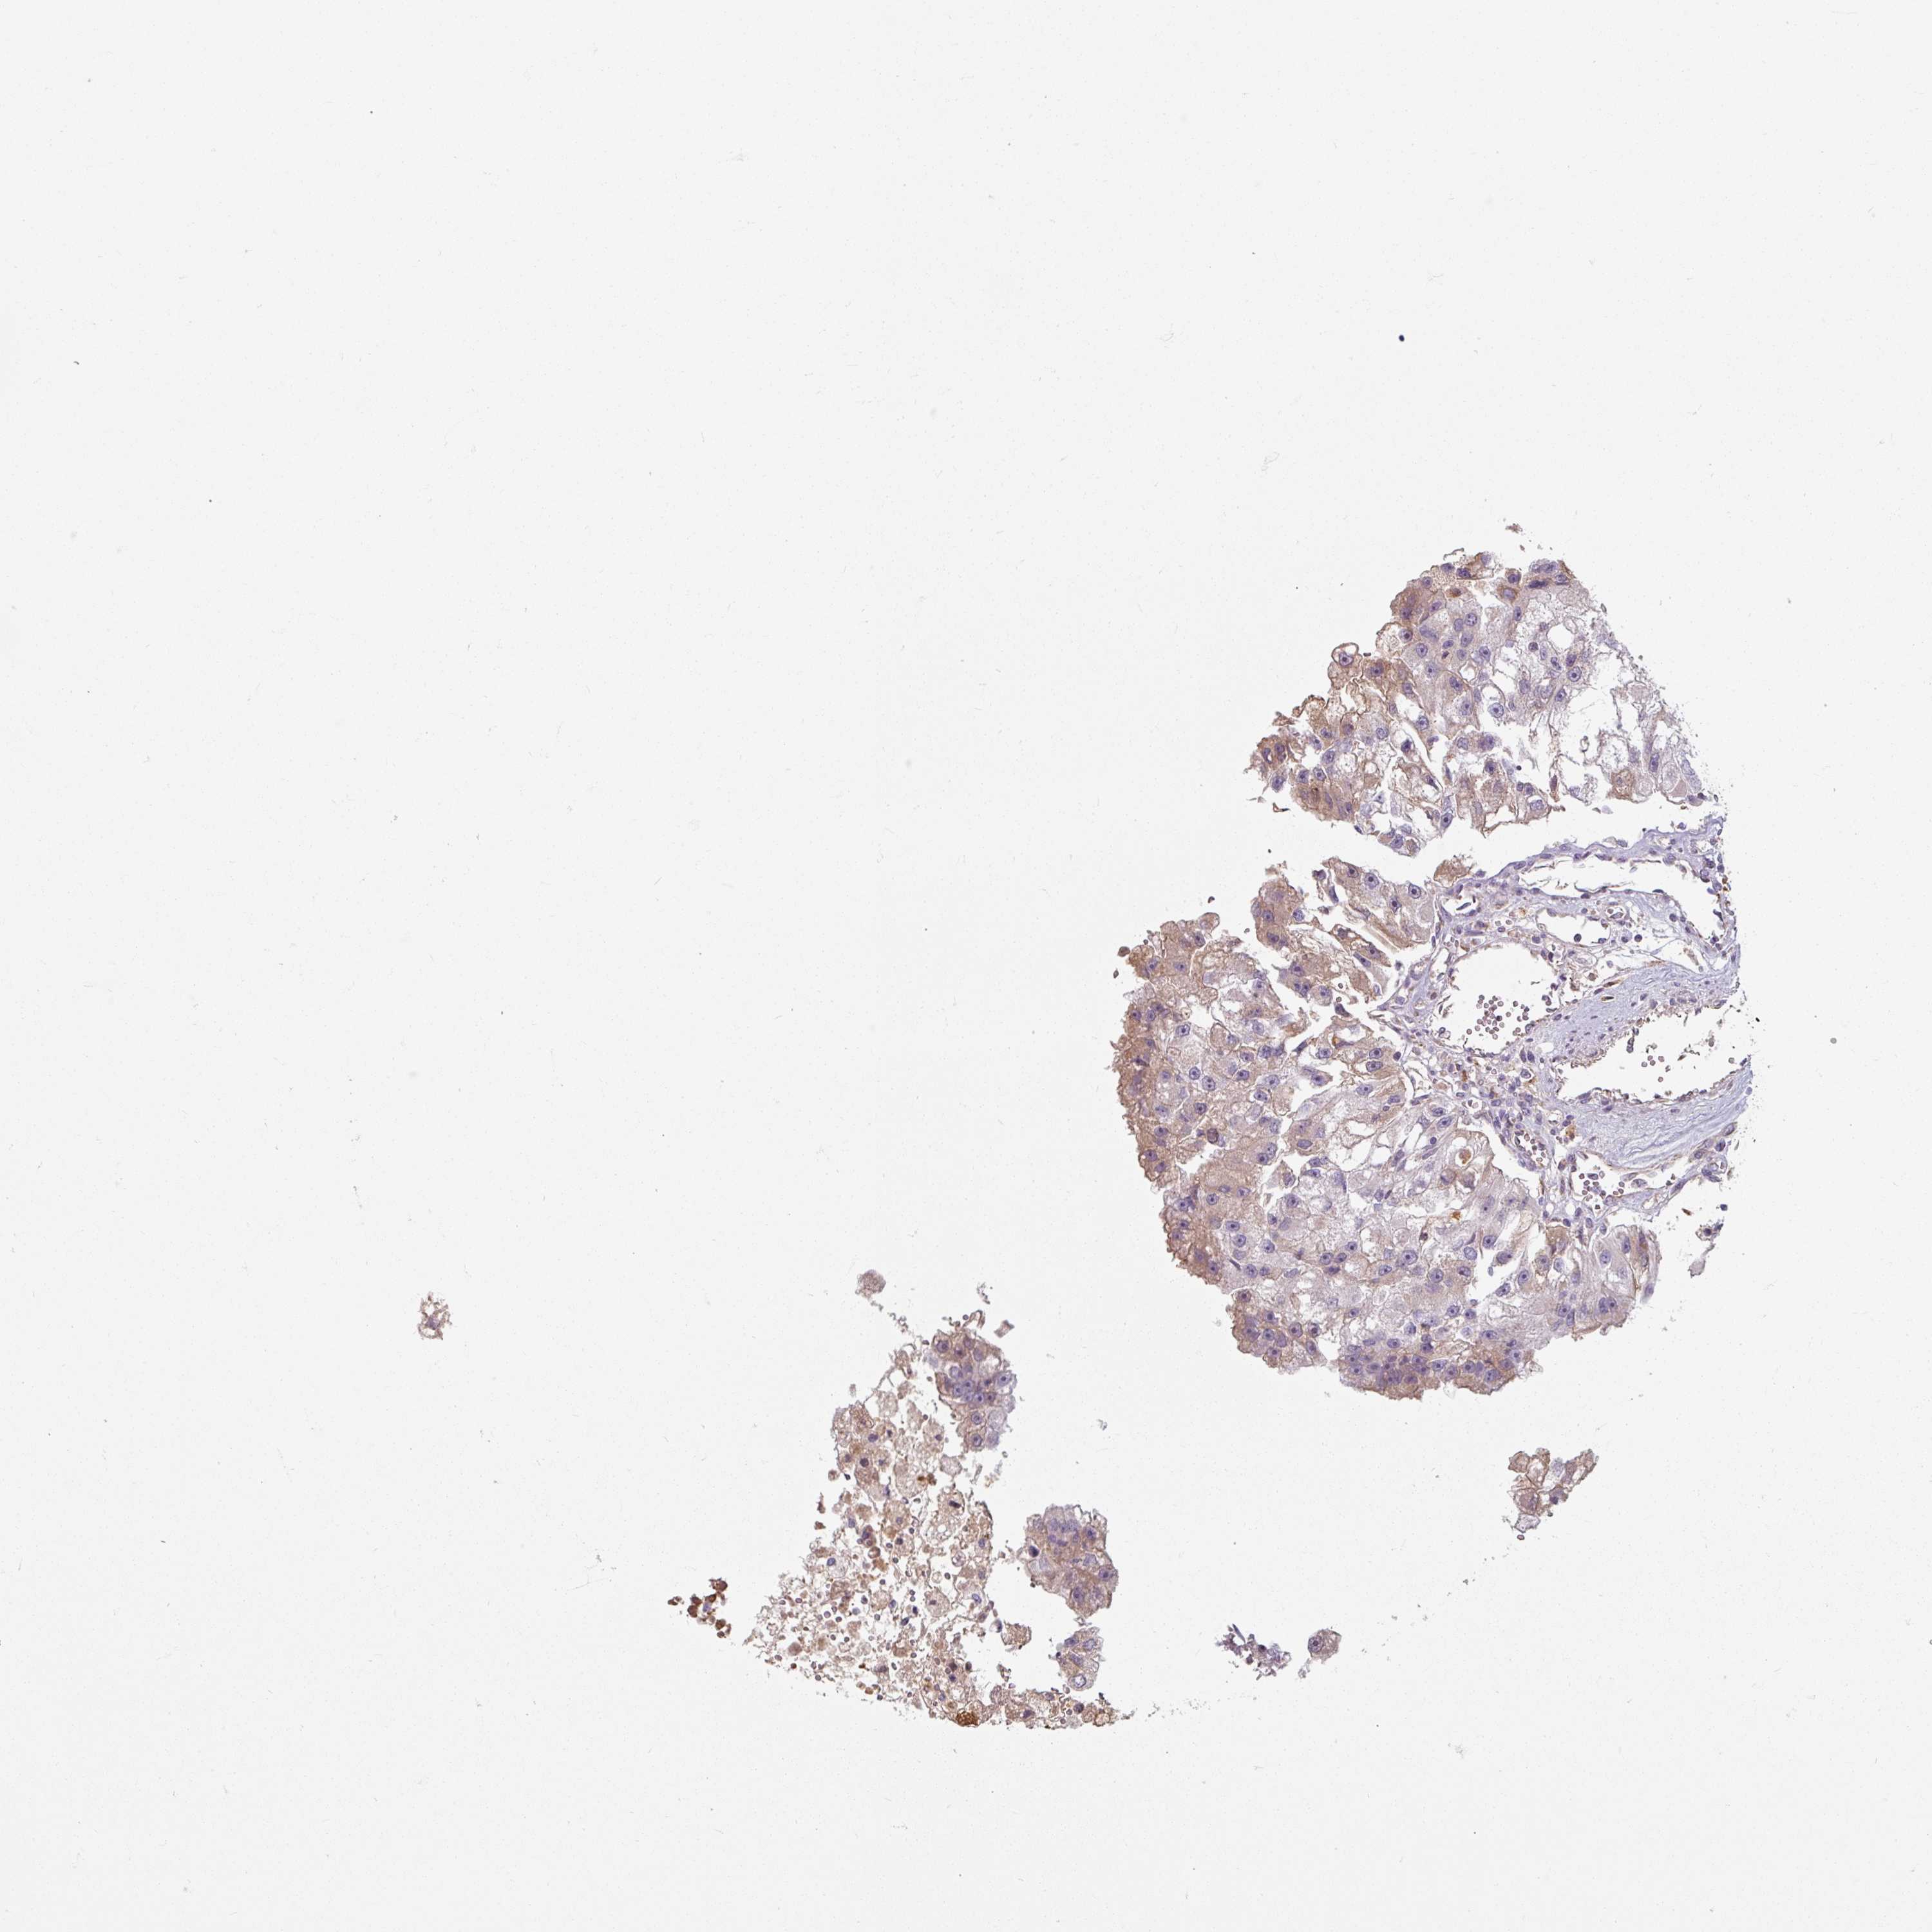

KIDNEY RENAL CLEAR CELL CARCINOMA (VALIDATION) - Interactive survival scatter ploti

The Survival Scatter plot shows the clinical status (i.e. dead or alive) for all individuals in the patient cohort, based on the same data that underlies the corresponding Kaplan-Meier plots. Patients that are alive at last time for follow-up are shown in blue and patients who have died during the study are shown in red.

The x-axis shows the expression levels (FPKM) of the investigated gene in the tumor tissue at the time of diagnosis. The y-axis shows the follow-up time after diagnosis (years). Both axes are complimented with kernel density curves demonstrating the data density over the axes. The top density plot shows the expression levels (FPKM) distribution among dead (red) and alive patients (blue). The right density plot shows the data density of the survived years of dead patients with high and low expression levels respectively, stratified using the cutoff indicated by the vertical dashed line through the Survival Scatter plot. This cutoff is automatically defined based on the FPKM cutoff that minimizes the p-score. The cutoff can be changed by dragging the vertical line or by entering a cutoff value in the square labeled "Current cut-off".

Under the Survival Scatter plot the p-score landscape (black curve; left axis) is shown together with dead median separation (red curve; right axis). Dead median separation is the difference in median mRNA expression between patients who have died with high and low expression, respectively. It is calculated as follows: median FPKM expression of dead patients with high expression - median FPKM expression of dead patients with low expression. This is intended to aid the user in visually exploring custom cutoffs and the associated p-scores and dead median separation.

Individual patient data is displayed and can be filtered by clicking on one or more of the category buttons on the top of the page. Categories describing expression level and patient information include: high, low, alive, dead, female, male and tumor stages. The scale of the x-axis can be toggled between linear and log-scale by clicking on the "x log" button. Mouse-over function shows TCGA ID, patient information and mRNA expression (FPKM) for each patient.

& Survival analysisi

Kaplan-Meier plots summarize results from analysis of correlation between mRNA expression level and patient survival. Patients were divided based on level of expression into one of the two groups "low" (under cut off) or "high" (over cut off). X-axis shows time for survival (years) and y-axis shows the probability of survival, where 1.0 corresponds to 100 percent.

TSEN54 is not prognostic in Kidney Renal Clear Cell Carcinoma (validation)

Best expression cut offi

Based on the FPKM value of each gene, patients were classified into two groups and association between prognosis (survival) and gene expression (FPKM) was examined. The best expression cut-off refers the FPKM value that yields maximal difference with regard to survival between the two groups at the lowest log-rank P-value. Best expression cut-off was selected based on survival analysis .

When clicking on this number, the vertical dashed line indicating cut-off, the interactive survival plot, and the Kaplan-Meier curve will be adjusted to show results based on the best expression cut-off.

: 8.84

P scorei

Log-rank P value for Kaplan-Meier plot showing results from analysis of correlation between mRNA expression level and patient survival.

N/A

TCGA RNA samplesi

RNA-seq data is reported as average FPKM (number Fragments Per Kilobase of exon per Million reads), generated by the The Cancer Genome Atlas (TCGA) .

Normal distribution across the dataset is visualized with box plots, shown as median and 25th and 75th percentiles. Points are displayed as outliers if they are above or below 1.5 times the interquartile range. FPKM values of the individual samples are presented next to the box plot.

Average pTPM 9.0

Number of samples 100